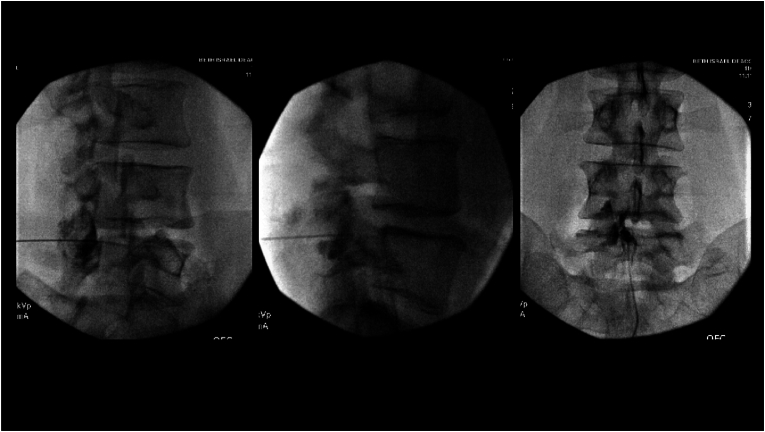

2. Fluoroscopic guidance: Same setup as TFESI — AP view to identify level, then oblique to visualize the foramen

3. Needle placement: Same periforaminal target as TFESI, using a 22-25 gauge spinal needle

4. Contrast injection first: Inject 0.1-0.3 mL of contrast to confirm position and observe the spread pattern — critical to verify limited, localized spread

• A retroneural approach with more lateral needle tip placement improves selectivity by directing injectate to the spinal nerve

• Diagnostic SNBs require unique targeting more laterally at the foramen with severely limited injection volumes to prevent distribution into the central epidural space medially or the plexus laterally.